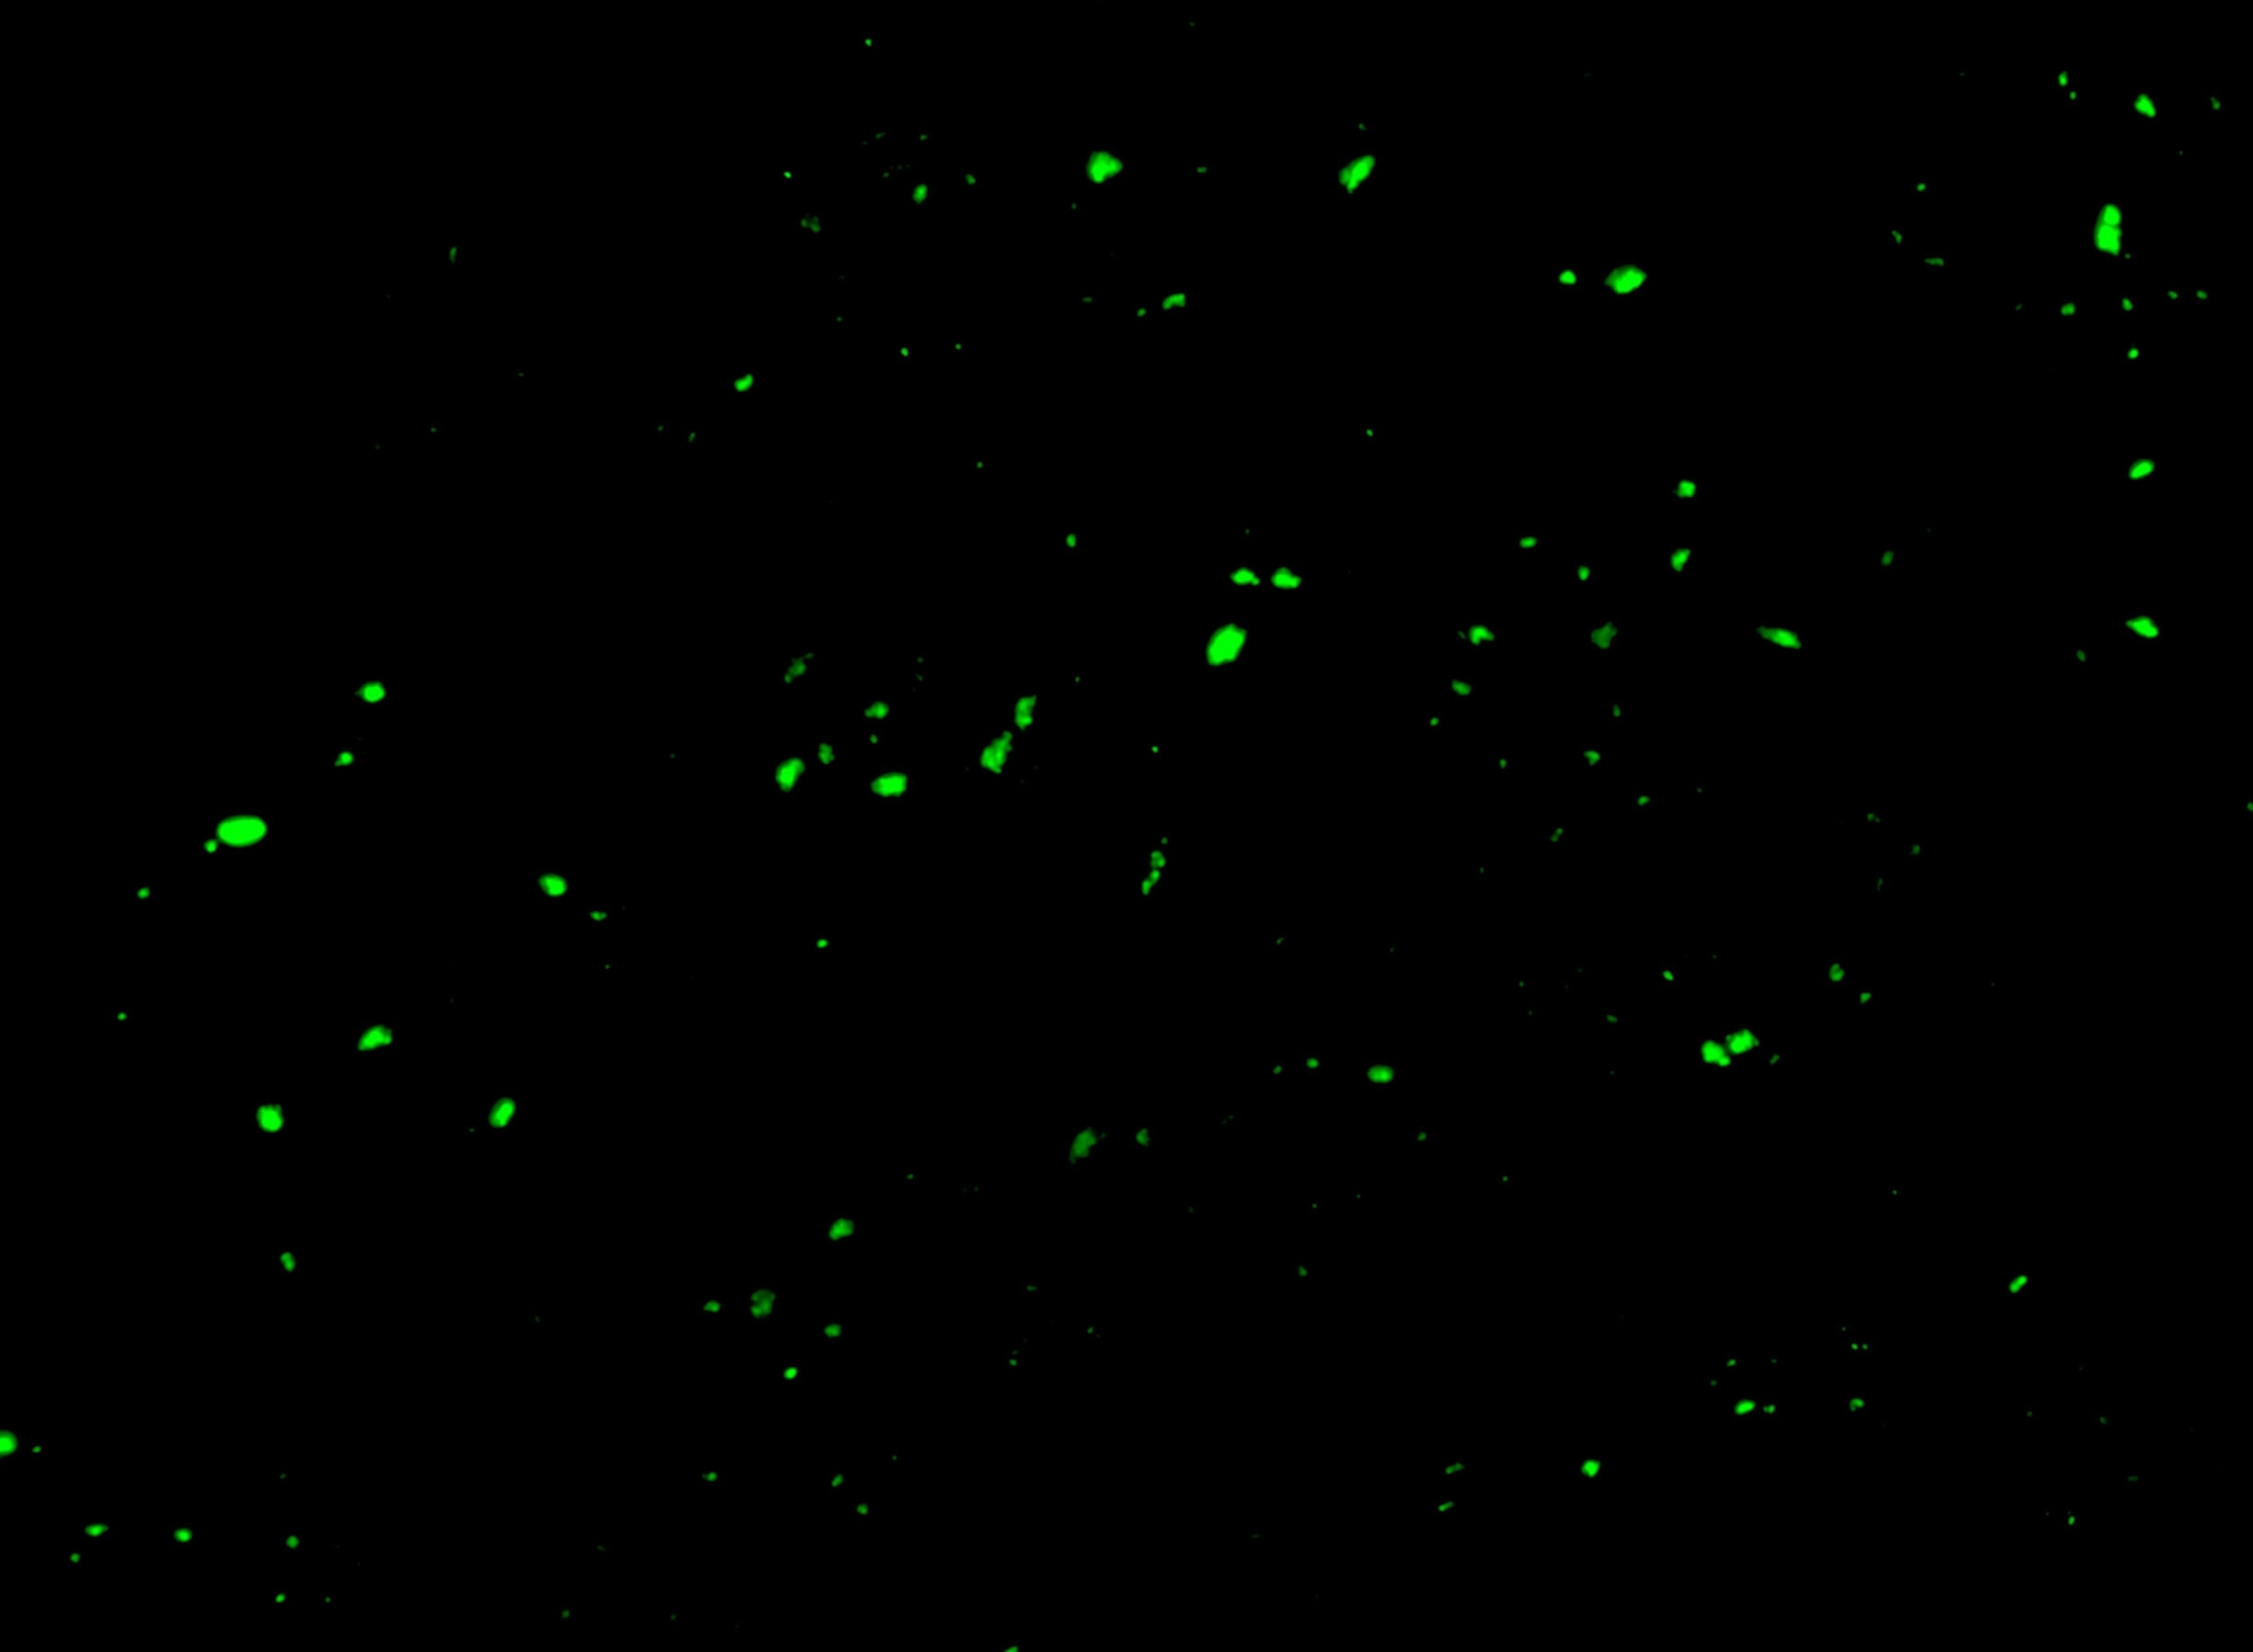

When she first saw the microscope images of fluorescent green blobs revealing the microclots, she cried with relief. For her, the confirmation that she has microclots felt like validation of her illness, “especially after not getting a PCR test at the beginning and being gaslit throughout the last few years.”

Detecting microclots requires a specialized laboratory technique called fluorescence microscopy. “You can’t just go to the doctor’s office and get tested for microclots,” says microbiologist Amy Proal, of the nonprofit PolyBio Research Foundation and co-founder of the long COVID Research Initiative.

The process involves drawing blood, spinning it, and adding a fluorescent agent to see the clots under a fluorescence microscope. It’s not a widely available tool in general pathology labs.

For now, Putrino and his team are seeing a correlation between the number of microclots on a microscope slide and the severity of a patient’s cognitive impairment. These include their ability to regulate emotions, plan and put together long-term solutions to problems, or figure out ways to deal with real-time situations as they’re changing. The research team is also developing an objective measure for microclots. “We’re still at a very rudimentary stage,” Putrino says.